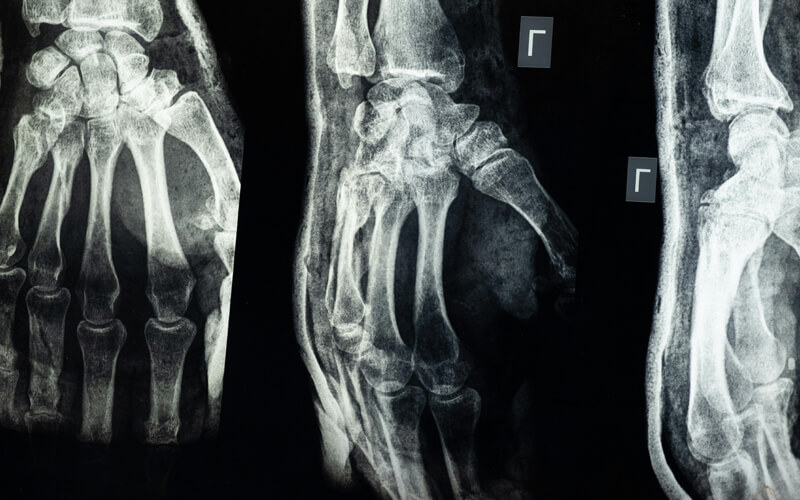

Imagen. / Los rayos X fueron uno de los avances más influyentes en la tecnología médica del siglo XX. © Cottonbro Studio.

Los rayos X constituyen una herramienta indispensable para el diagnóstico clínico no invasivo. Uno de sus usos más comunes es la detección de fracturas óseas, dado que los huesos absorben gran parte de los rayos y se presentan como áreas blancas en las imágenes. En el campo de la neumología, la radiografía torácica permite identificar infecciones pulmonares, como la neumonía, o enfermedades crónicas como la EPOC. También se emplean en la localización de cuerpos extraños, evaluación dental, y análisis de condiciones gastrointestinales mediante estudios contrastados con bario.